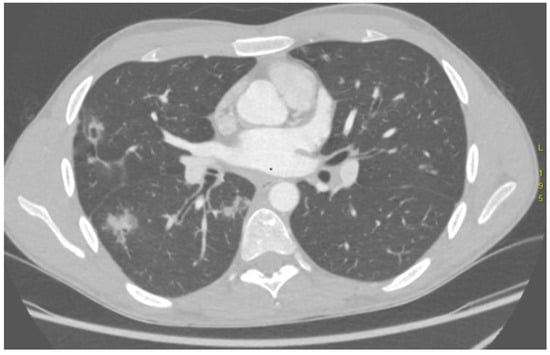

| Case Number | Computed Tomography Angiography Findings | Culprit Vessel Identified on Digital Subtraction Angiography | Match |

|---|---|---|---|

| P07 | Dilated, tortuous R BA (up to 4 mm) and L BA Diffuse GGO (especially in LLL) | 2 × R BA | Yes |

| P09 | Dilated R BA with suspected anastomosis to pulmonary artery, dilated L BA | R BA | Yes |

| P10 | GGO in S3 of RUL | 2 × R BA | Yes |